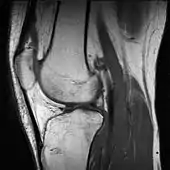

علاوه بر این، از انواع رنگ کاذب مانند شبهرنگ، برش چگالی و کروپلتها برای تجسم اطلاعات یا دادههای جمعآوریشده توسط یک کانال در رنگ خاکستری (سیاه-سفید) یا دادههایی که بخشی از طیف الکترومغناطیسی را نشان نمیدهند، استفاده میشود (بهعنوان مثال ارتفاع در نقشههای برجسته یا انواع بافت در تصویربرداری تشدید مغناطیسی)

بسته به جدول یا عملکرد مورد استفاده و انتخاب منابع داده، شبهرنگ آمیزی ممکن است محتوای اطلاعات تصویر اصلی را افزایش دهد، بهعنوان مثال افزودن اطلاعات جغرافیایی، ترکیب اطلاعات بدستآمده از نور فروسرخ یا فرابنفش یا منابع دیگر مانند پویش تصویر تشدید مغناطیسی (MRI).[14]